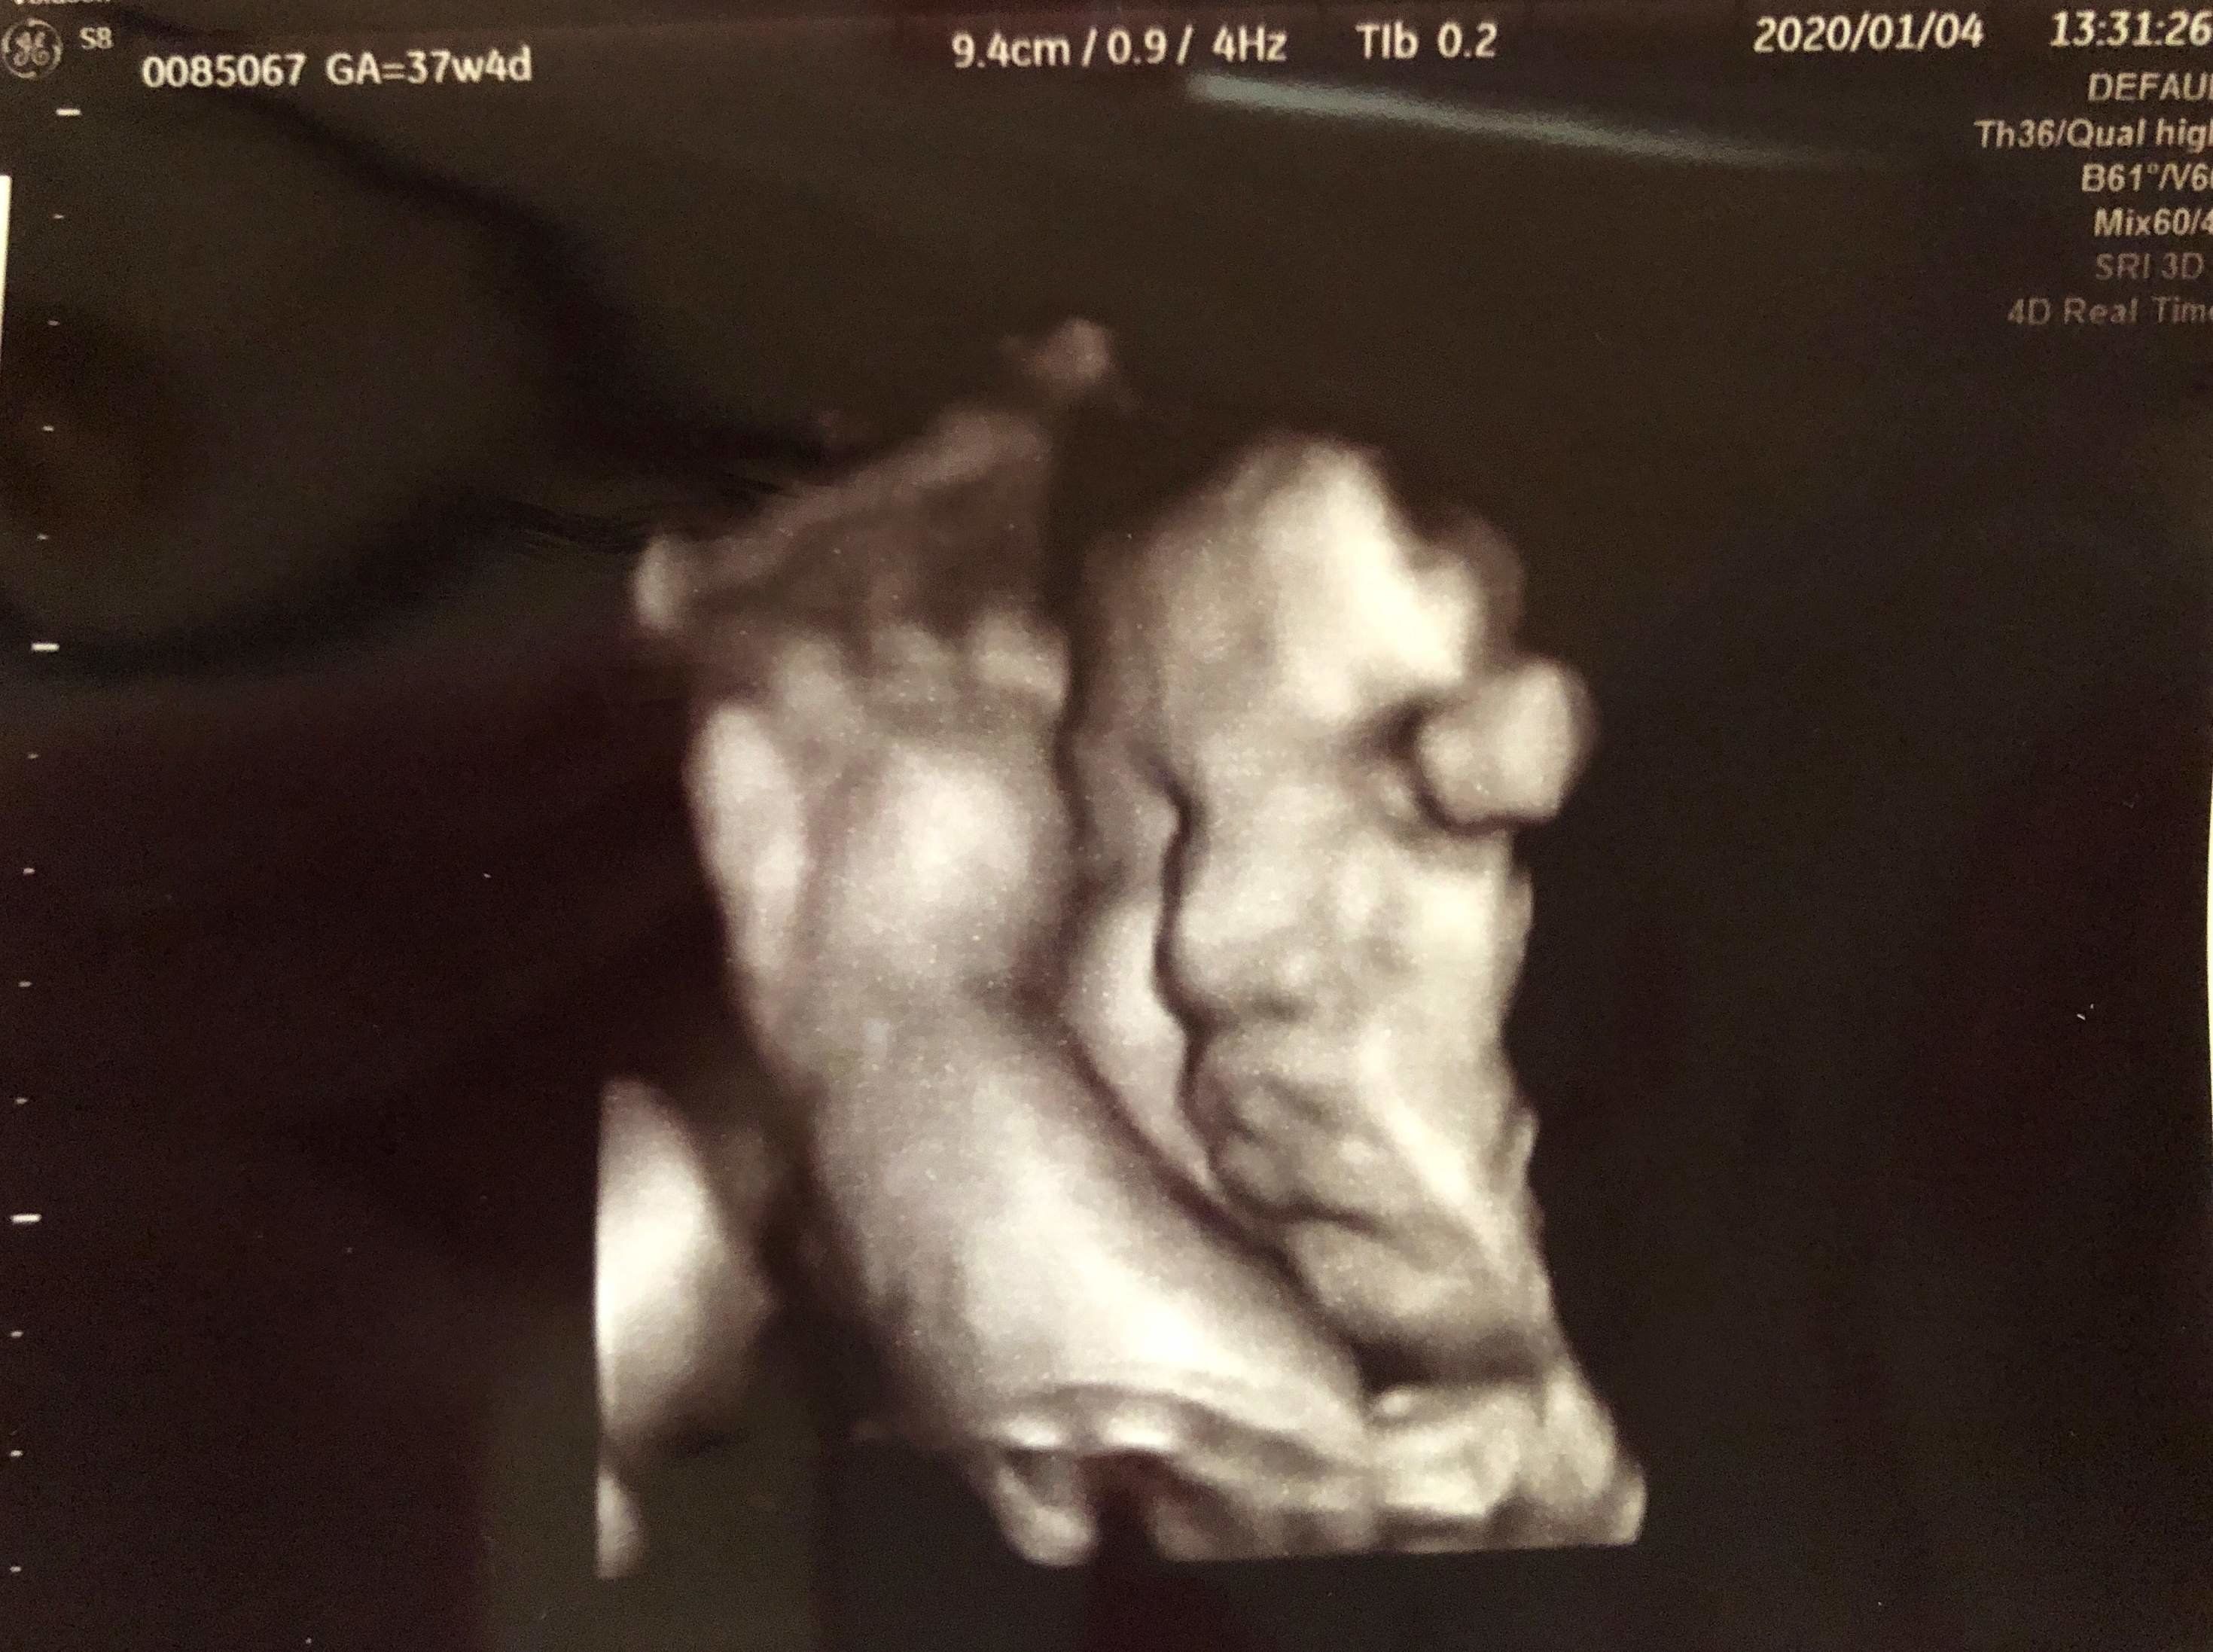

妊娠37週目 計画出産をすることに

あっという間に正期産となり、いよいよ出産が近づいてきました。里帰りはしない予定だったので、出産・入院の間の長男のお世話のことも考え、先生や家族と相談の結果、計画出産をすることにしました。赤ちゃんは予定日ギリギリまでおなかで過ごせたほうがいいとのことで、入院は妊娠39週に決定。

エコーで見た次男の横顔と長男の寝顔がそっくりで、夫と「すごく似ているね」と笑いながら、次男が生まれるのを心待ちにしていました。